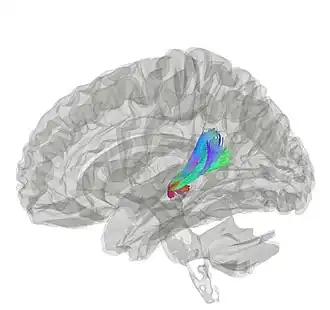

Acoustic radiation

Human auditory pathway. Acoustic radiation is shown as red arrow at center-top. | |

The acoustic radiations or auditory radiations are structures found in the brain, in the ventral cochlear pathway, a part of the auditory system.[1][2] Acoustic radiation arising in the medial geniculate nucleus and end in primary auditory cortex (transverse temporal gyri). Lesions to the auditory radiations could be a cause of cortical deafness.[3]